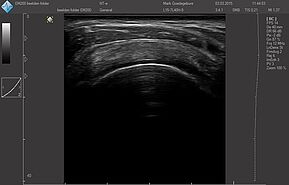

Области исследований:

- Брюшная полость

- Акушерство и гинекология

- Урология

- Щитовидная железа

- Молочная железа

- Кардиология

- Костно-мышечная система

- Педиатрия

- Нейросонография

- Исследование сосудов

- Транскраниальные исследования

Датчики имеют большую чувствительность и высокое разрешение, благодаря чему обеспечивают максимальное проникновение и улучшают соотношение сигнал /шум. В результате формируется максимально четкая детализированная картинка УЗИ изображения.